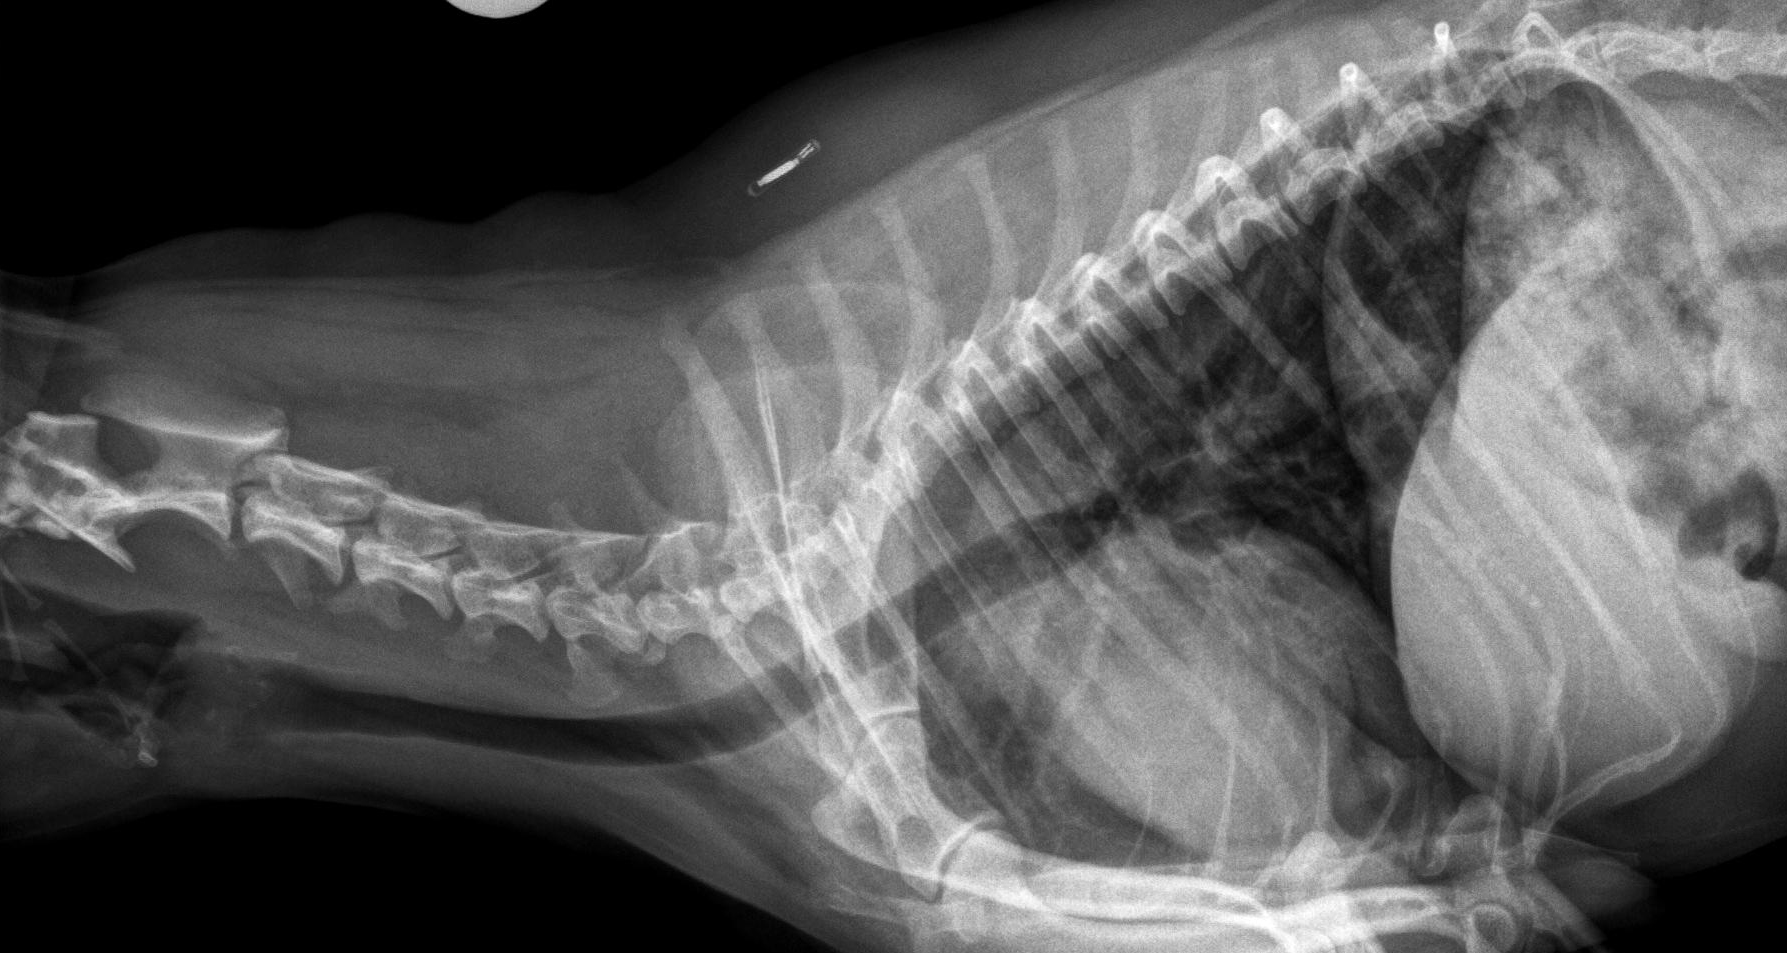

Latérale